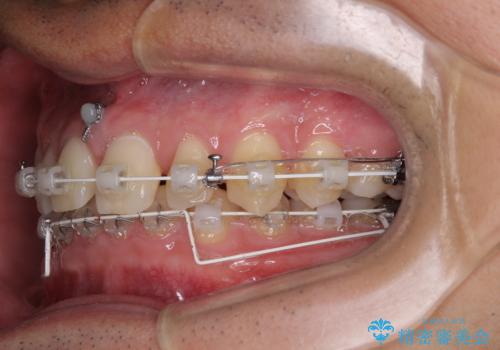

アンカースクリューを用いて下に位置している上顎前歯を持ち上げるとともに、ワイヤー装置によりディープバイトの原因である奥歯の傾斜を改善することで、矯正治療を行っていくこととしました。

顕著なディープバイトのため、頻繁に装置が脱離することがあり、治療期間が想定よりも長くかかることがありますが、当初の予定期間で無事に治療を終えることができました。